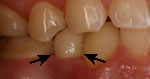

Implants are generally considered as an alternative

to Dentures, Partials,

or Bridges. When replacing a missing tooth

in the front of the mouth, nothing looks more natural than an implant.